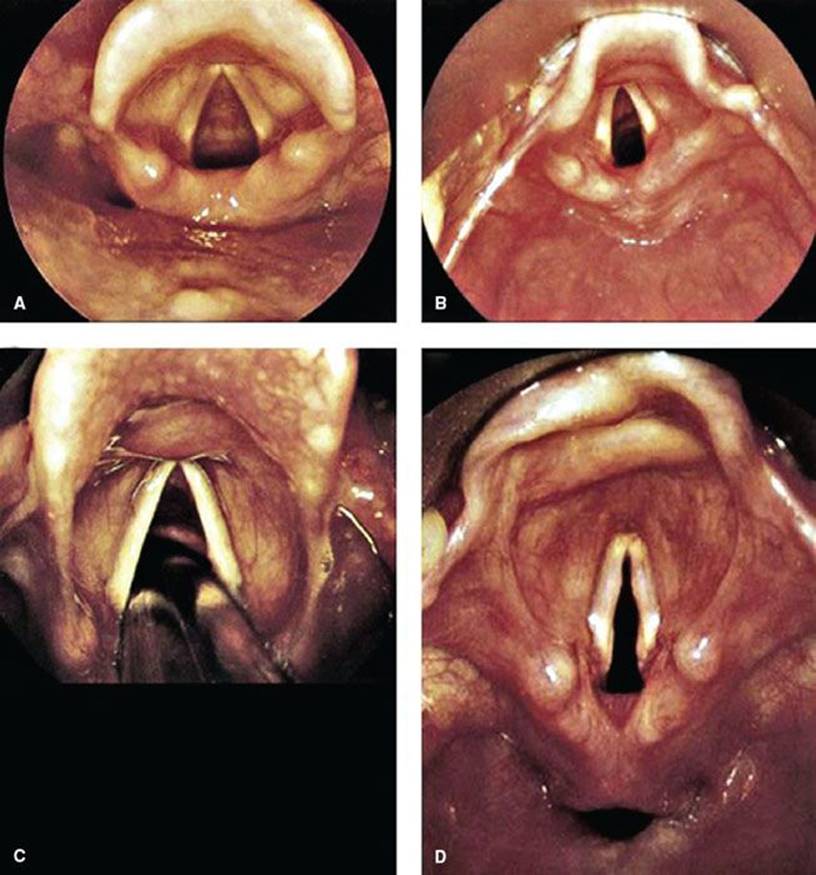

Video-assisted devices are becoming more commonplace in EDs, particularly in the training environment. There have been many studies to date that have shown users obtain better laryngeal visualization and have a higher first-pass success rate in the difficult airway patient (6). There are many commercially available video laryngoscopes and all require some added training. Even in the hands of novice video laryngoscopy improves visualization and visual confirmation of proper tube placement (eFig. 19.2). Intubation can be performed by passing a tube over a flexible fiberoptic scope while visualizing the vocal cords or using a rigid video laryngoscope, such as the Glidescope or Storz video system. The same principles of RSI apply when using a video device.

eFIGURE 19.2 Larynx appearance with videolaryngoscope. A: Preintubation view of an adult airway. B: Preintubation view of a pediatric airway. C: ETT passing between the vocal cords. D: The larynx and hypopharynx (note the horizontally oriented space below the laryngeal inlet, which is the esophagus). (From Nagdev A. Airway, breathing, circulation: Normal airway. In: Greenberg MI, Hendrickson RG, Silverberg M, et al., eds. Greenberg’s Text-atlas of Emergency Medicine. Philadelphia, PA: Lippincott Williams & Wilkins; 2004, with permission.)